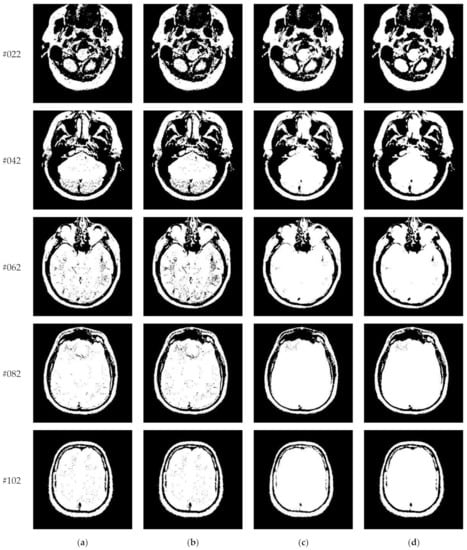

This subsection compares segmentation results of different algorithms (Proposed, Otsu, IIMT, and HL-IIMT) on images containing noise. Figure 13 displays five images with Gaussian noise N (0, 0.001) added to images #022, #042, #062, #082, and #102, which were selected from Figure 9.

Figure 13.

Images containing noise via the addition of Gaussian noise N (0, 0.001): (a) slice #022, (b) slice #042, (c) slice #062, (d) slice #082, (e) slice #102.

Figure 14 displays the segmentation results of images containing noise with a single level of thresholding K = 1. It can be observed that segmentation results achieved by HL-IIMT and Proposed are distinctly better than those of Otsu and IIMT, which have many isolated points. Figure 15 depicts segmentation results obtained by different algorithms with multilevel thresholding K = 4. Obviously, segmentation results of Otsu, IIMT, and HL-IIMT are seriously affected by noise, and most regions are blurred. However, the results of Proposed are better, and they have less noise and clearer edges.

Figure 14.

Segmentation results obtained by different segmentation algorithms for images containing noise (K = 1): (a) Otsu, (b) IIMT, (c) HL-IIMT, (d) Proposed.

Figure 15.

Segmentation results obtained by different segmentation algorithms for images containing noise (K = 4): (a) Otsu, (b) IIMT, (c) HL-IIMT, (d) Proposed.

A comparison of the evaluation results for different segmentation algorithms on images containing noise with K = 1, 4 is shown in Table 3, and corresponding comparison charts are given in Figure 16. In Table 3, the best results are marked in bold. It can be noted that Proposed consistently has the highest U values. For images containing noise, both the IIMT-based algorithms (HL-IIMT and Proposed) are superior to the original Otsu method in single threshold segmentation; furthermore, Proposed can achieve satisfactory results in multilevel threshold segmentation compared to the other three algorithms (IIMT, HL-IIMT, and Otsu).